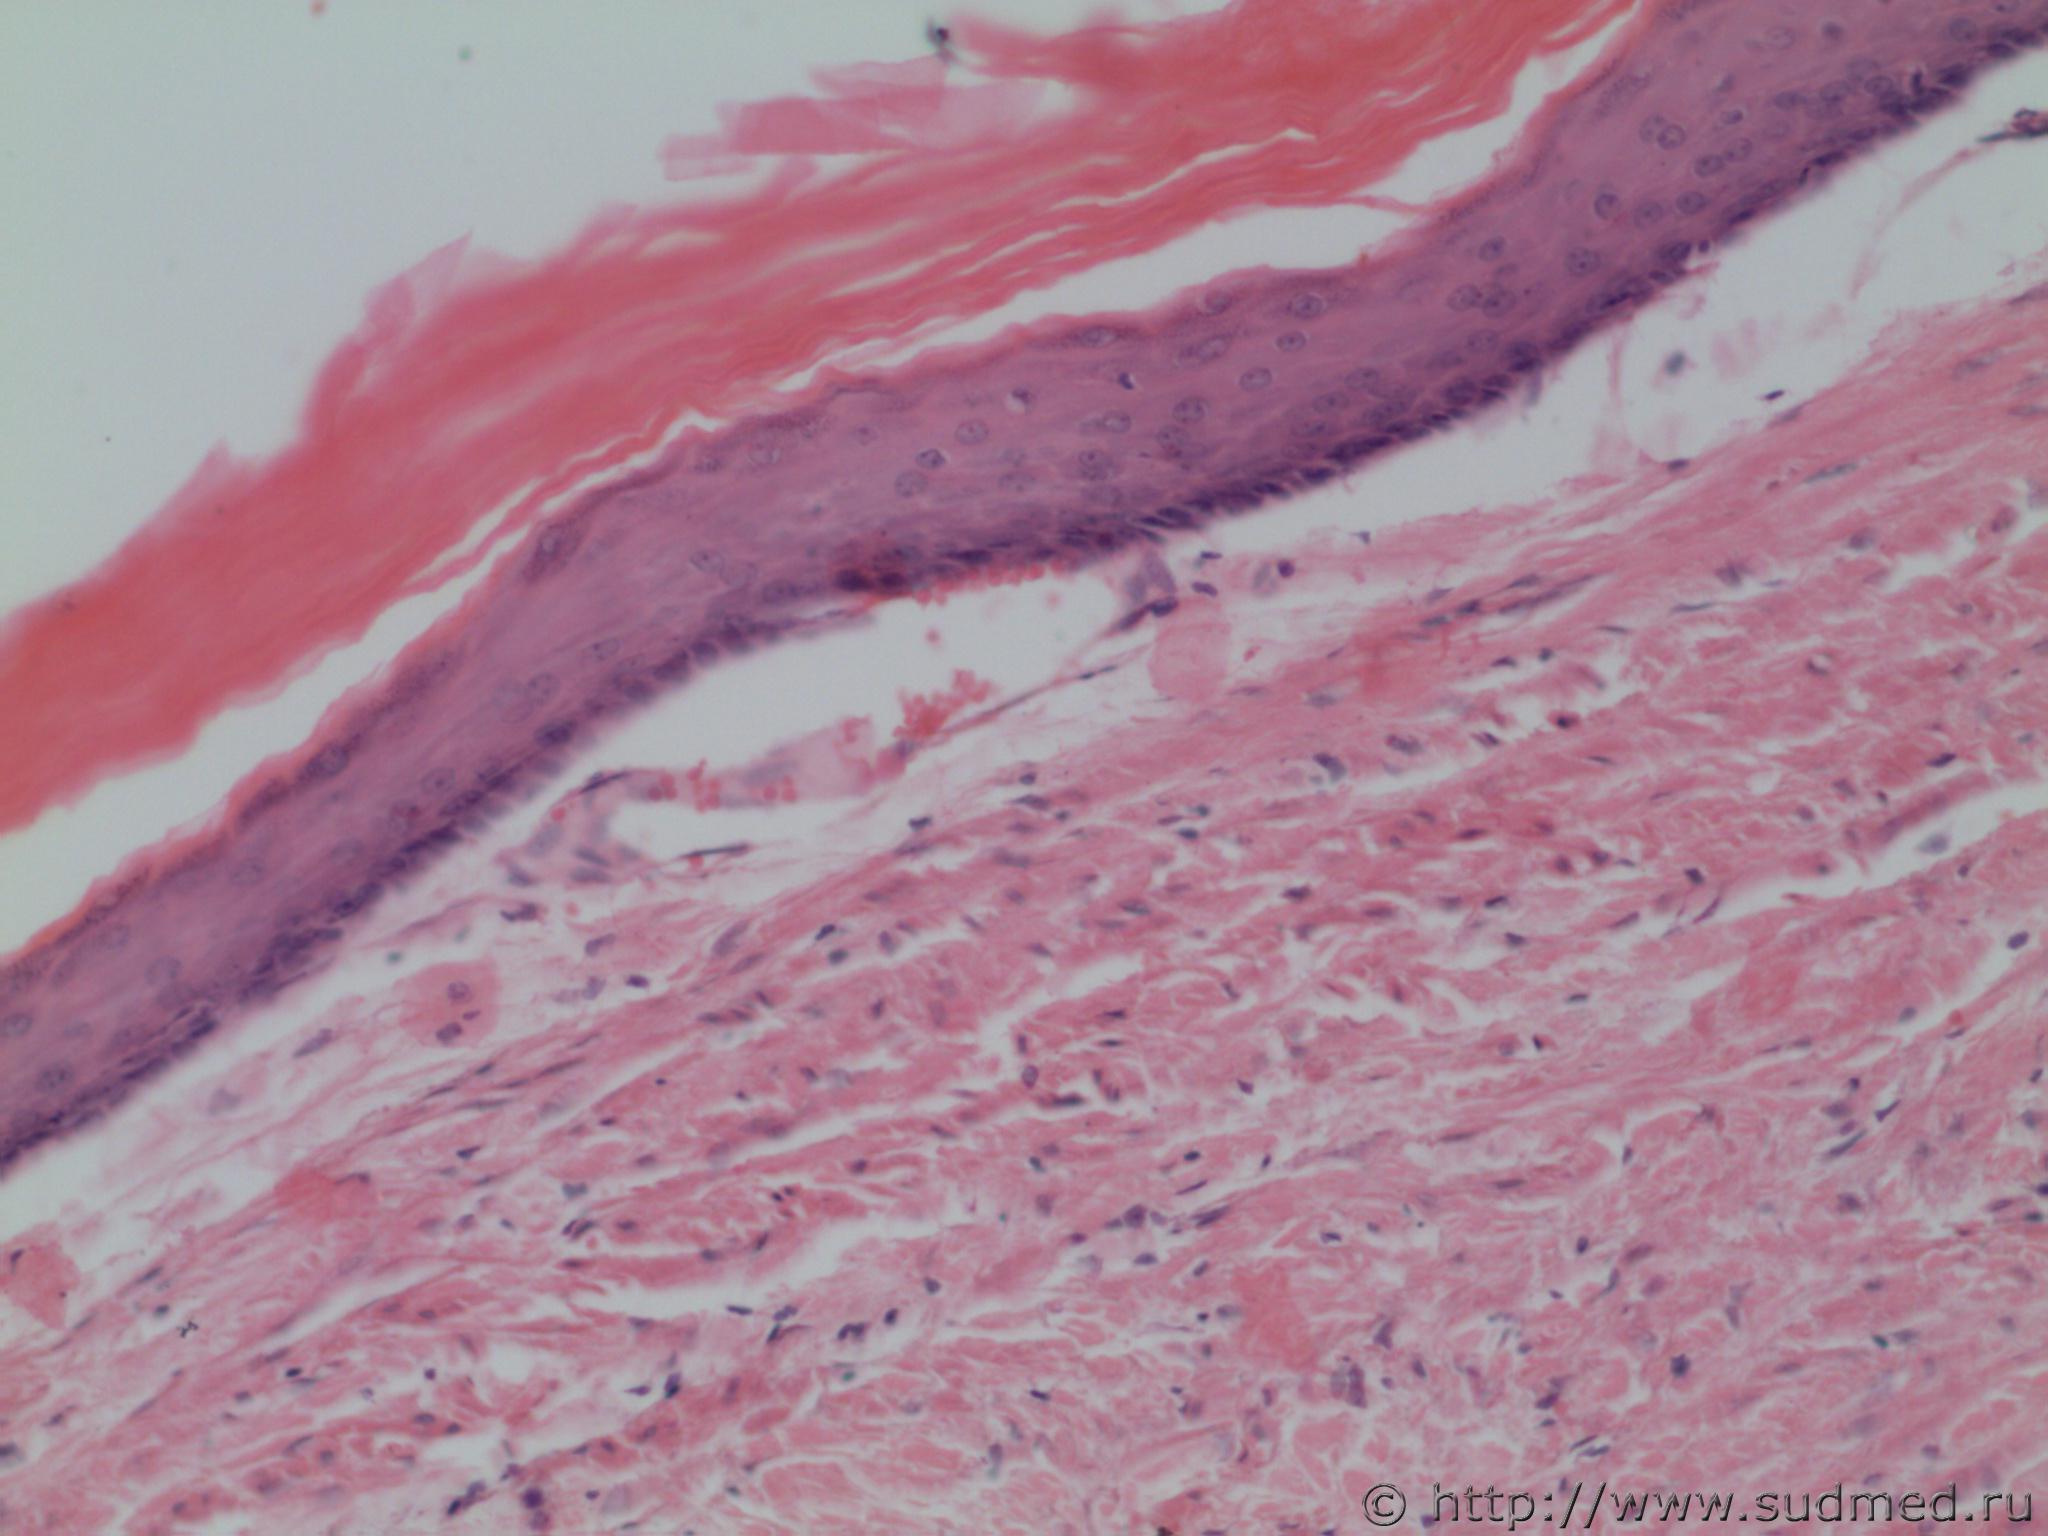

Трубная беременность (внематочная)

Плоскоклеточная метаплазия эндометрии